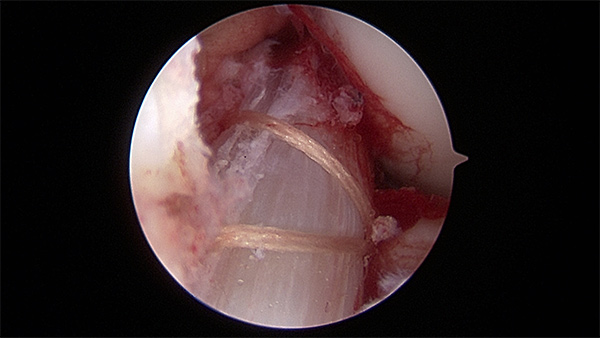

Arthroscopic view of a torn ACL (image courtesy of Dr. Eric Makhni)

ACL reconstruction using a BTB autograft in a 15 year old elite soccer player (image courtesy of Dr. Eric Makhni)